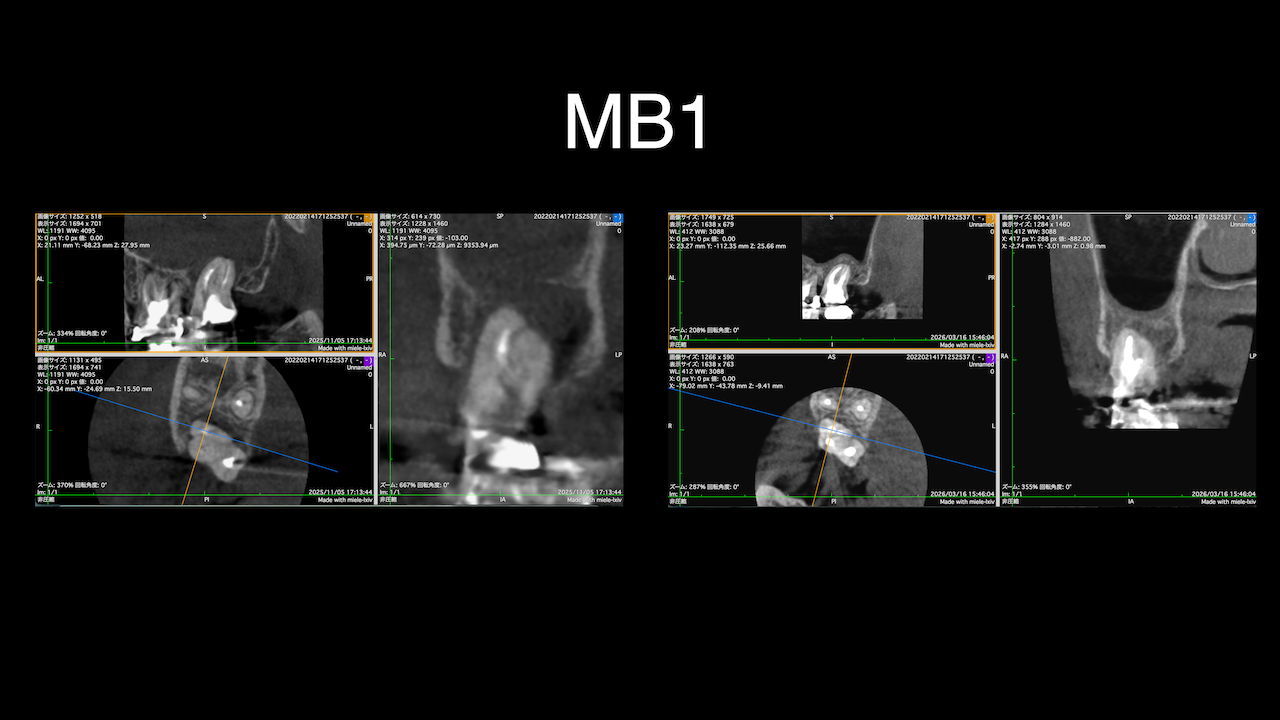

次は北九州で開業されているK先生。

術前にCBCTを撮影したので、MB2がないということを分かった上で根管治療を行っている。

これがCBCTを歯内療法に用いる最大の利点だろう。

上手い!

この先生の1年前は以下だったそうだ。